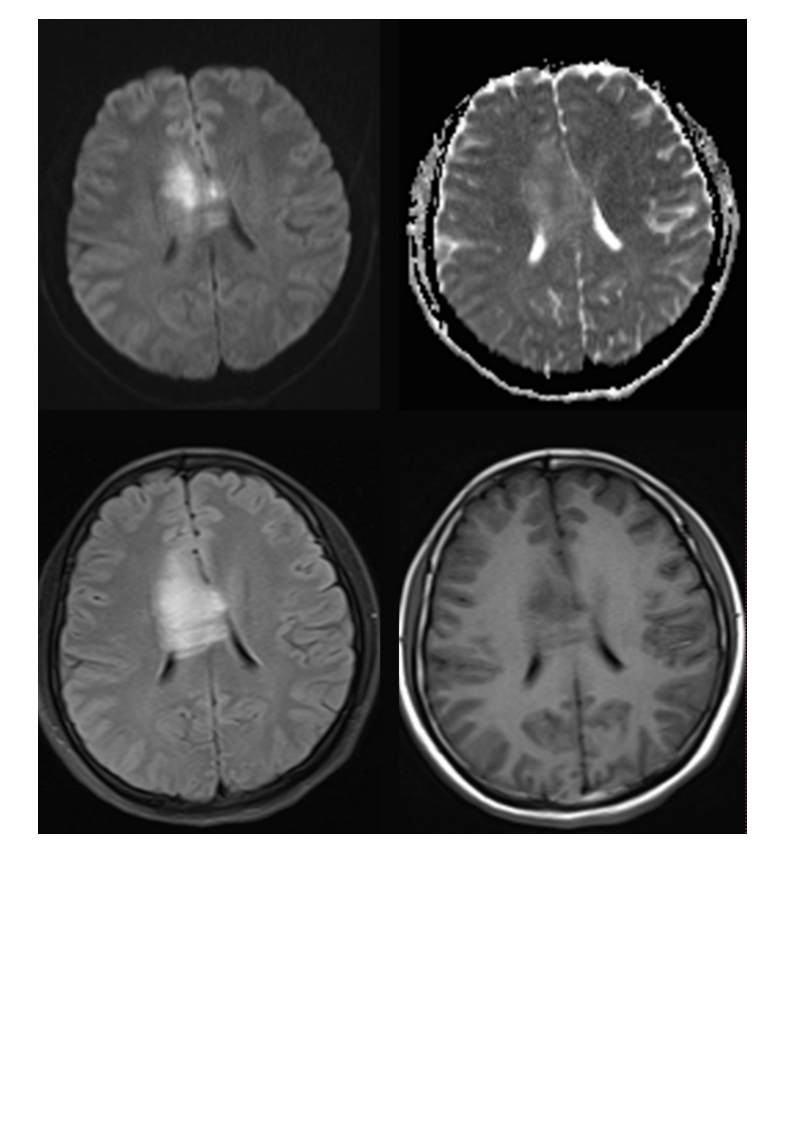

20210608_2【晨读结果公布】2021.06.07神经系统疾病——病例1:间变型少突胶质细胞瘤;病例2:PCNSL;病例3:胼胝体急性梗死.pdf